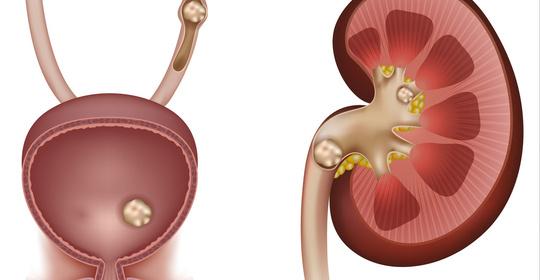

陰囊腫脹:男性健康暢談,認知陰囊腫脹的原因與應對

前列腺硬結:男性健康警示,及時瞭解與調理

睪丸下垂:男性生殖器睪丸下垂的生理與可能病理原因!

無睪丸:男性生殖健康詳解,診斷與治療全方位!

睪丸微小:男性健康預警,症狀及其背後的原因解析